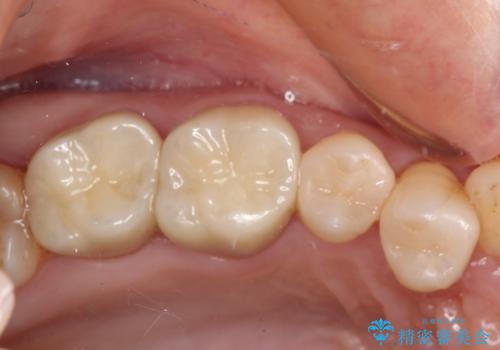

- 奥歯の銀歯をセラミックの白い歯にして、しみる症状も改善したいとのことで来院された患者様です。

知覚過敏の症状が強い歯と、銀歯の範囲や銀歯の下のむし歯が大きい歯は、インレー修復では対応が難しいためオールセラミッククラウンで、インレー修復で対応が可能な歯ではセラミックインレーにて修復することとしました。

知覚過敏の症状はなくなり、希望通りの白い歯になったと、患者様は大変満足されました。